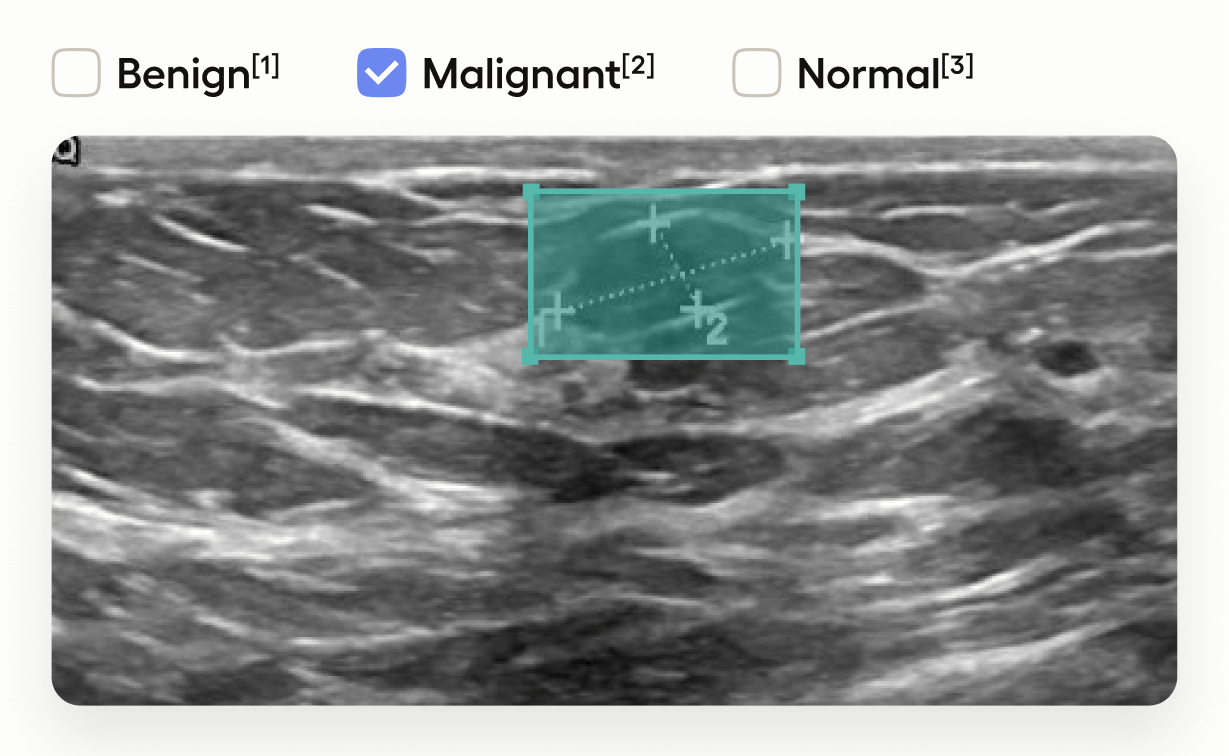

- Draw bounding boxes around areas identified as tumors in the image using the “Tumor” label.

- Classify the entire image by selecting one of “Benign”, “Malignant”, or “Normal”.

This setup is useful in medical imaging tasks where you need to localize tumors and also provide an overall assessment of the image.

</RectangleLabels>This defines the image segmentation you can use. In this template, you’re drawing rectangles (bounding boxes).

- The

RectangleLabelstag creates a tool for drawing bounding boxes, andtoName="image"means that the boxes will be associated with the tag namedimage(which in this example is the name assigned to the<Image>tag). - The

Labeltag specifies that the bounding boxes represent “Tumor” regions, displayed with a green background.

</Choices>This adds image-level classification choices.

- The

<Choices>tag provides a set of options for annotators to select. toName="image"applies these choices to the entire image.- Annotators can classify the image as “Benign”, “Malignant”, or “Normal”.